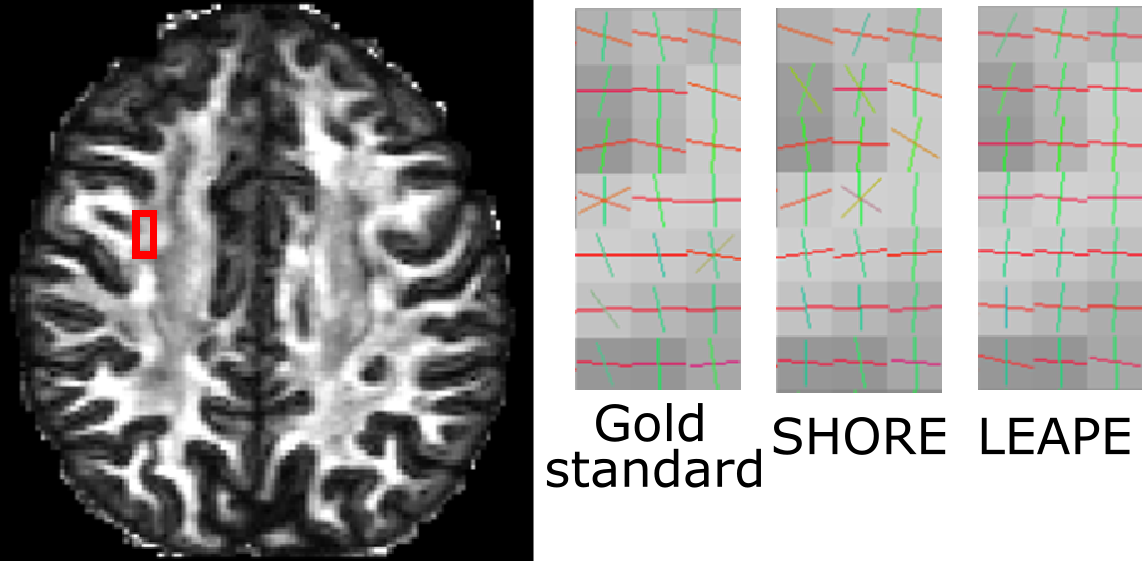

A straightforward strategy for EAP estimation would be to modify the MLP in [4] by giving vectors of coefficients at the output layer. However, typical loss functions, such as the mean squared error used in [4], cannot guarantee to properly capture the structure of the coefficients, which could lie in a non-Euclidean space. For example, we observed that the extraction of directional information of ODFs and FOs from the EAPs can be problematic with such a strategy. Fig. 1 gives an example of the ODF and FOs (overlaid on fractional anisotropy (FA)) extracted from the EAPs estimated using this simple strategy. The horizontal peak of the ODF is not preserved, and incorrect FO configurations with missing FOs can be observed. Even if a loss function that properly defines the difference of EAP coefficients can be discovered, computing its gradient in the training process can be nontrivial.

Next, we evaluated the FOs extracted from the EAP. A qualitative comparison is made in Fig. 5, where we focus on a region where the corpus callosum (CC) and superior longitudinal fasciculus (SLF) cross. We can see that the LEAPE result resembles the gold standard, and LEAPE better resolves crossing FOs and produces smoother FOs than SHORE. The LEAPE FOs are even smoother than the gold standard in some cases. We also computed the average FO disagreement with the gold standard in the white matter for SHORE and LEAPE (see Fig. 4). Note that if the second MLP in LEAPE is not used for training, the FO errors range from to (not shown in Fig. 4), and for every subject the errors are higher () than those of SHORE or LEAPE. This indicates the benefit of adding the second MLP. Compared with SHORE, the mean and median of the disagreement of LEAPE are smaller. The difference of disagreement between SHORE and LEAPE is small. This is possibly because for the less complicated FO configurations (for example, noncrossing FOs), which occupy a large proportion of the white matter volume, both SHORE and LEAPE are able to produce good results with 60 diffusion gradients, and the difference like the one shown in Fig. 5 is present at regions with more complex FO configurations.